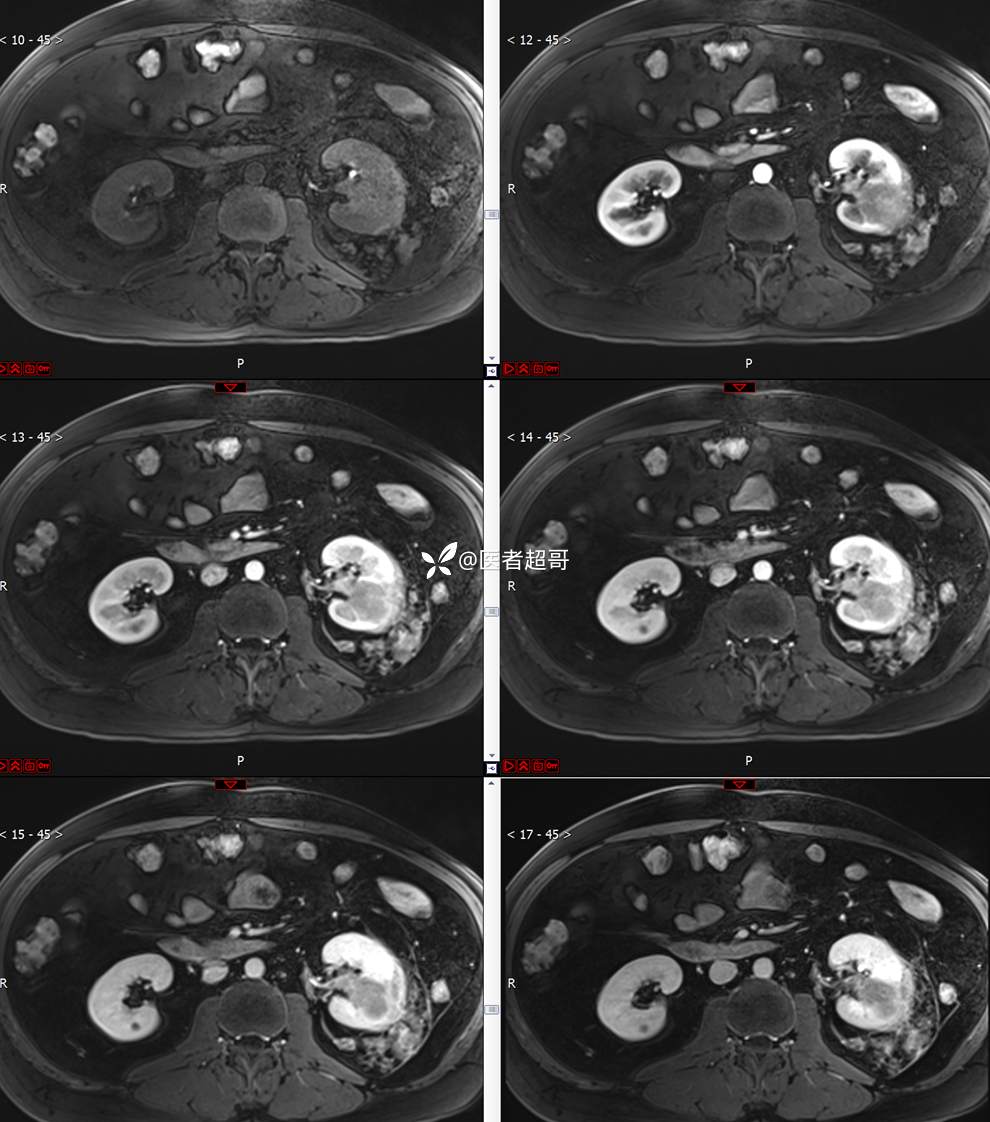

主 诉:查体发现左肾肿物9天。

现病史:患者9天前于附属医院行常规腹部CT检查时,发现左肾占位性病变并肾周脂间隙软组织增多,自述无明显腰腹部不适,无尿频、尿急、尿痛及肉眼血尿,未予特殊治疗,患者近期无头晕头迷,胸闷气急,腹胀腹泻及其他部位明显不适,遂至我院就诊,门诊以“肾肿物”收入院,患者自发病以来,精神可,睡眠饮食可,大便正常,体重无明显减轻。